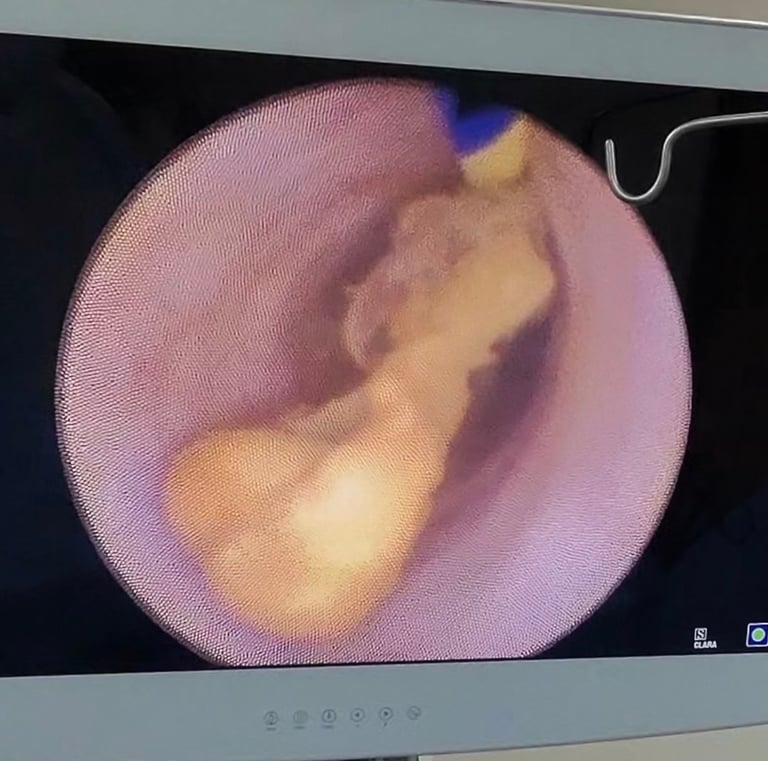

Galería

Imágenes que reflejan cuidado y confianza.